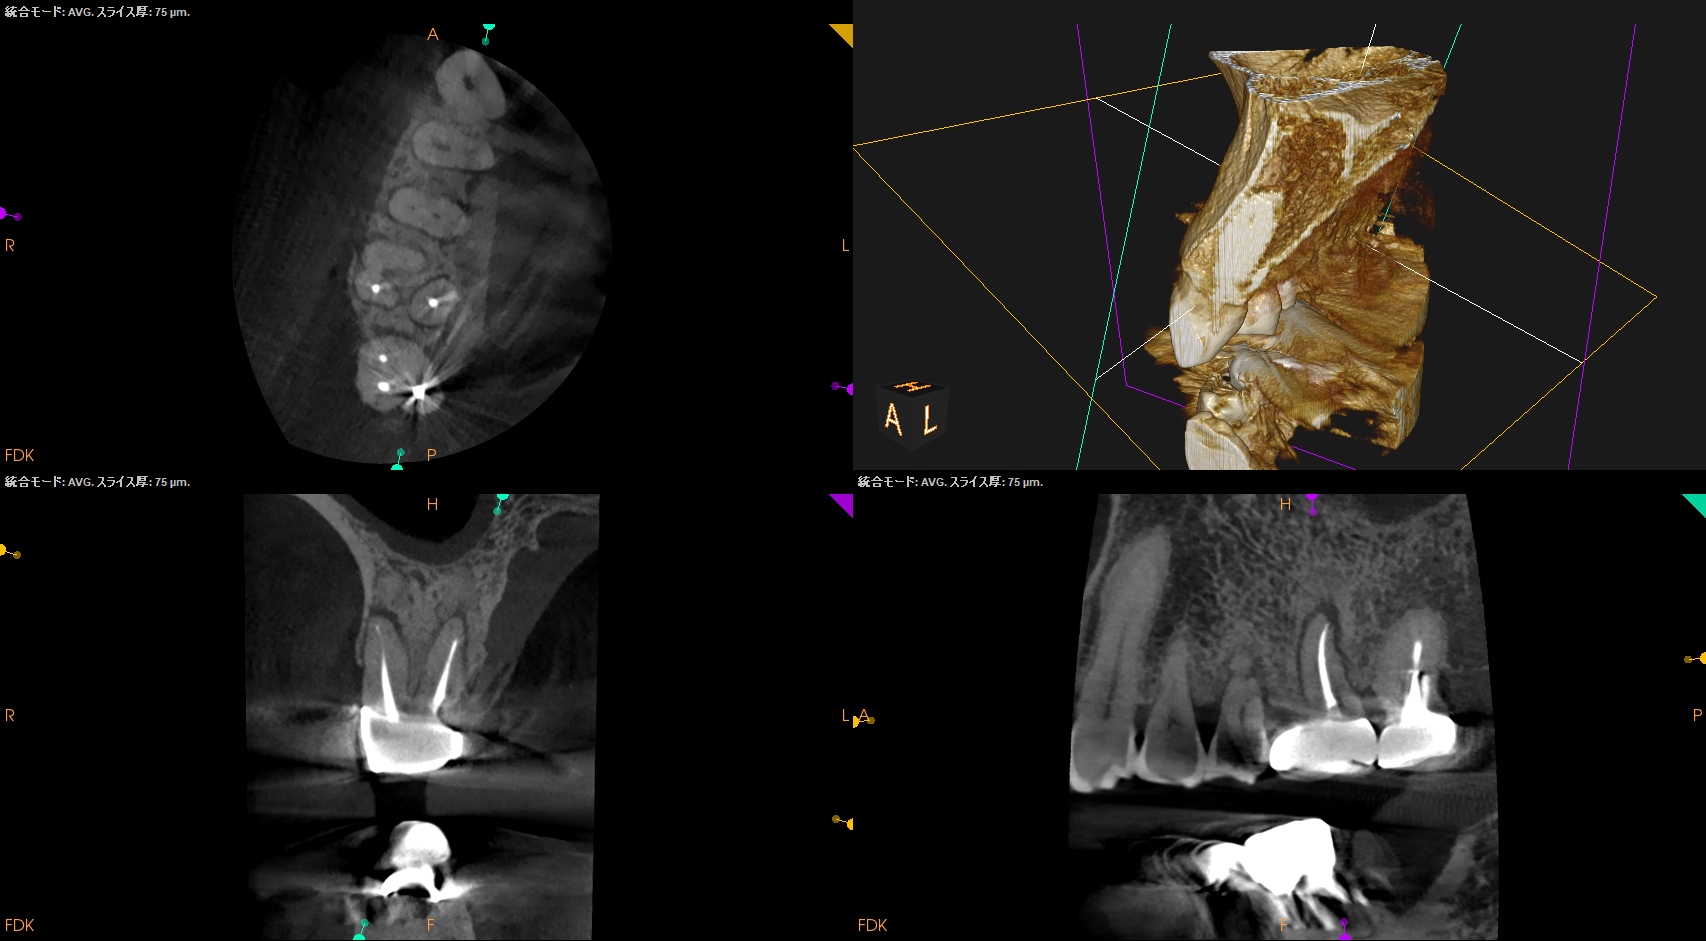

Pre-op CBCT(2024.11.25)

MB

DB

P

B

P根以外のMB,DBには根尖病変がありSinus tractがある。

ということは…

MB+DB Apicoectomyだ。